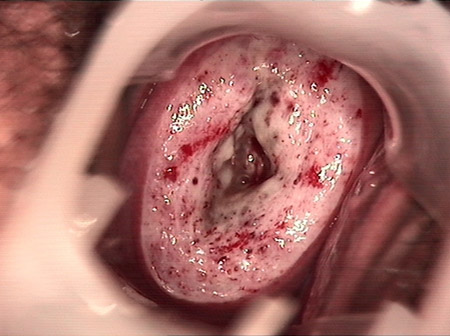

婦科leep錐切手術 CIN2-3

• CIN 2-3 修復后CIN 2-3 修復后